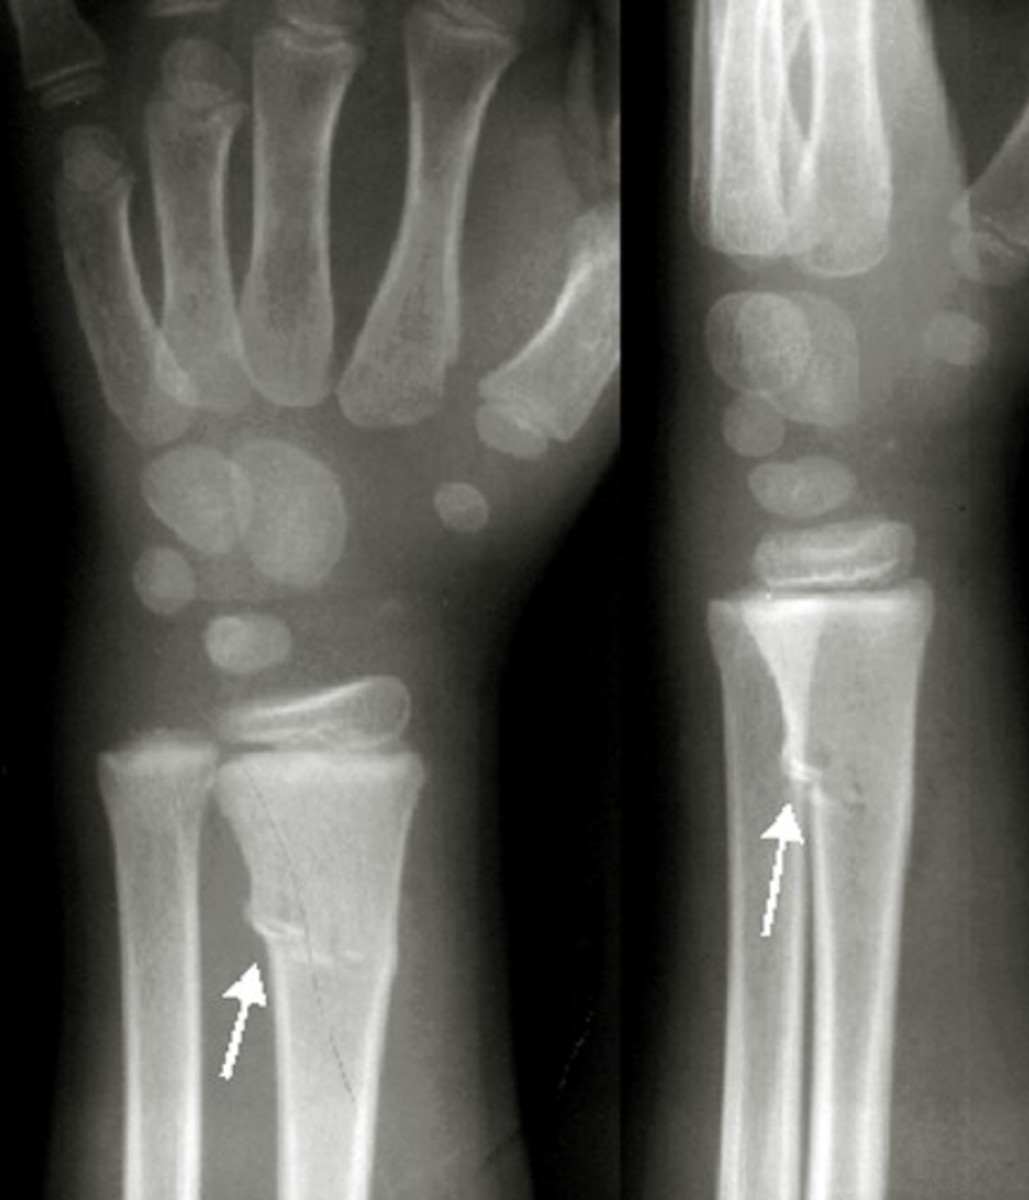

Buckle (Greenstick) Fracture of the Distal Radius Sports Medicine Review

Greenstick Fracture fracture, with cortical breach of only Greenstick Fracture Sports Example this activity reviews the evaluation, management, and pathophysiology of greenstick fractures and highlights the role of the. What is a greenstick fracture? however, if there is a fracture with a cortical breach, it is termed a greenstick fracture if unicortical, or a complete fracture if. examples of sporting activities that increase the risk of a greenstick fracture. Greenstick Fracture Sports Example.